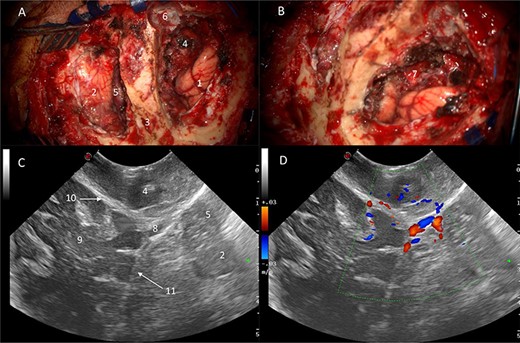

Power and colour Doppler were used throughout to obtain real-time information about the location and function of dural venous sinuses. Blood flow was preserved in the sinuses and, as we debulked the tumour, we were able to demonstrate bi-directional flow within the sinuses (Fig. 3). This suggested resolution of venous obstruction and indicated the dural venous sinuses had regained their functionality. Medially tumour was found invading the torcula and right transverse sinus, and a decision was made to leave the residual tumour and to preserve the sinuses (Fig. 4). We achieved a Simpson Grade 4 resection without any intraoperative complications.

Intraoperative images at the end of resection; Duplex US images (2D image with overlay of colour Doppler) of the initial appearances of the straight sinus (A) and appearance at the end of resection (B); a bidirectional flow in the straight sinus is apparent after tumour resection, this was not present prior to tumour debulking; the Triplex Doppler confirms the bidirectional flow in the straight sinus (C and D).

Correlation of US appearance and gross anatomy; (A and B) intraoperative picture of the surgical field at the end of resection; (C and D) final US assessment—B-mode (C) and duplex (D); 1, ipsilateral occipital lobe; 2, ipsilateral cerebellar hemisphere; 3, strip of bone on top of the transverse sinus; 4, supratentorial resection cavity; 5, infratentorial resection cavity; 6, torcular; 7, supra-infratentorial communication of the tumour via the tentorium; 8, straight sinus; 9, contralateral occipital lobe; 10, falx cerebri; 11, tentorium.